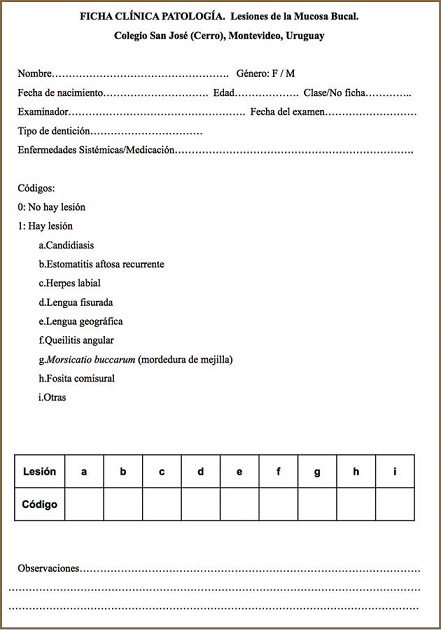

Procedimiento: se seleccionaron las 7 lesiones más frecuentes en la bibliografía consultada, se realizó el examen clínico para diagnosticar dichas lesiones siguiendo los lineamientos que plantean Bagan et al, (1995) para Morsicatio buccarum y Scully, (2008) para Candidiasis, Estomatitis aftosa recurrente, Herpes labial, Lengua fisurada, Lengua geográfica y Queilitis angular. Toda lesión que no estuviese incluida dentro del protocolo se incluyó en la categoría de “Otras”. El examen fue realizado por observadores calibrados (Índice Kappa = 0,96, 0,94, 0,94). Se utilizaron baja lenguas y espejos bucales para separar lengua, labios y mejillas; y una linterna vincha (Black Diamond) para iluminar el campo. Figura 1

Organización de datos: los datos fueron registrados en una ficha clínica diseñada específicamente para este estudio (Fig 1).